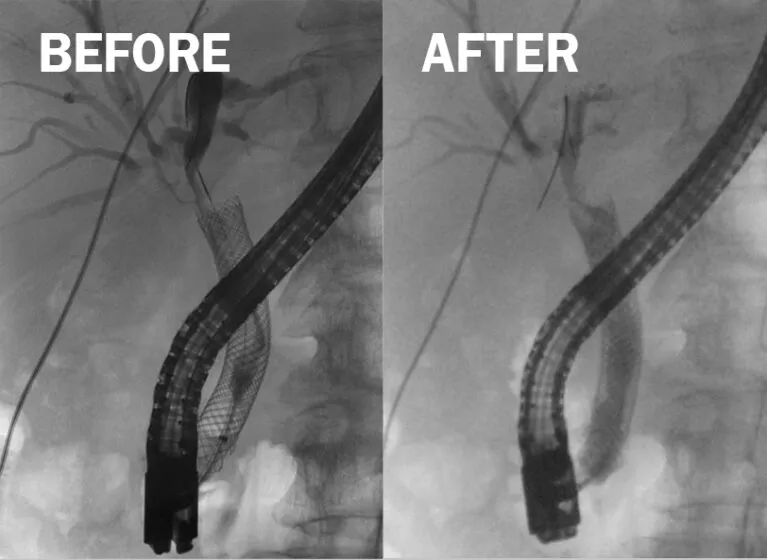

- Mgmt Flowchart: